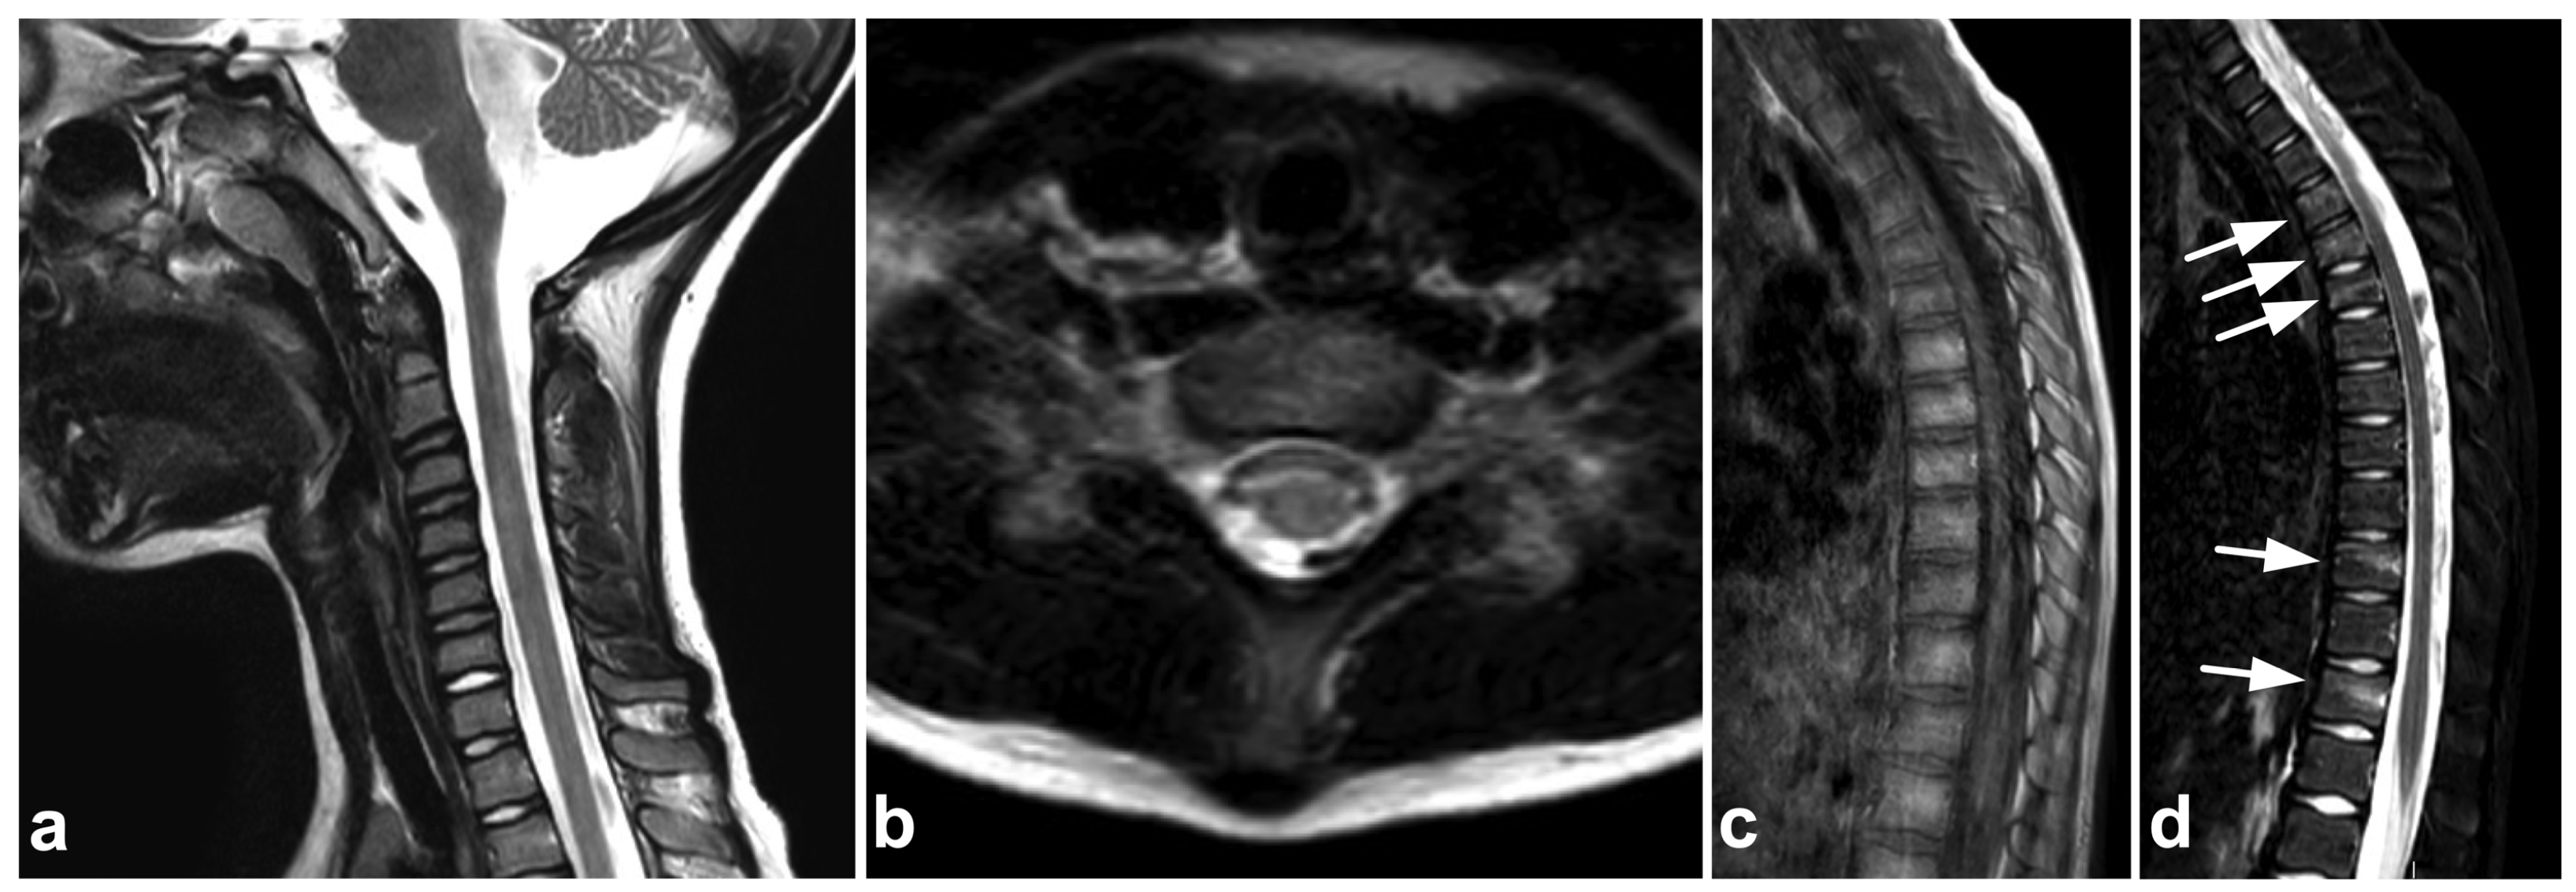

Spinal cord injury without radiographic abnormality (SCIWORA) is mainly seen in children, although it also exists in adults. The term was first described by Pang and Wilberger in 1982 [11], but symptomatic spinal cord injury without spinal fracture or dislocation was recognized even earlier [69]. SCIWORA is thought to occur due to the significant mobility and laxity of the spine in children, allowing self-reducing displacement to damage the cord [12]. The introduction and development of MRI have led to a terminological discussion evolving the concept of SCIWORA [13,70] by providing visibility to the cord itself and sometimes revealing structural injuries not seen in radiographs or CT [71]. Nevertheless, there seems to be a small number of patients with neurological symptoms from cord injury not visible in contemporary MR imaging, eventually with a favorable long-term outcome [12,72].

(a) Sagittal T2-weighted. (b) Coronal STIR. (c) Axial T2-weighted (dotted line in the image (a)). A 2-year-old female, severe cervical fracture–dislocation after a car accident. The spinal cord is transected. The cord caudally to the transection site (arrows) is dislocated posteriorly and on the right side of the cranial end of the transected cord (arrowhead). An extensive hematoma is seen around the fracture.

Figure 16.